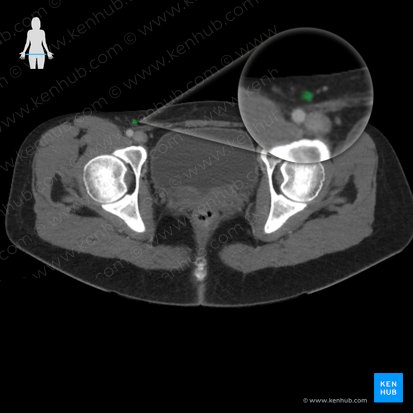

Inguinal lymph nodes

Inguinal lymph nodes are located within the inguinal region and receive lymphatic drainage from the lower extremity, genitals, dorsal perineum and the inferior most aspect of the anterior abdominal wall

They range from approximately 12-14 lymph nodes and are divided into superficial and deep groups.

The superficial inguinal lymph nodes, of which there are approximately 10, lie superficially, deep to the skin and Camper's fascia. They are located along the superficial circumflex iliac vein immediately below the inguinal ligament and are subdivided into the superomedial, superolateral and inferior superficial inguinal nodes. This group of lymph nodes receive lymphatic drainage from the anal canal (below the pectinate line), skin below the umbilicus, lower extremity, scrotum, and vulva. Efferent vessels of the superficial inguinal lymph nodes drain to either the deep inguinal nodes or external iliac nodes.

The deep inguinal lymph nodes lie within the femoral sheath, medial to the femoral vein and range from approximately 1-3 nodes. They are similarly divided into subgroups which include the proximal, intermediate and distal deep inguinal nodes. The deep inguinal nodes receive efferents from the deep lymphatics of the lower limb, superficial inguinal nodes and from the penis/clitoris. Efferent vessels of the deep inguinal nodes drain to the external iliac nodes.